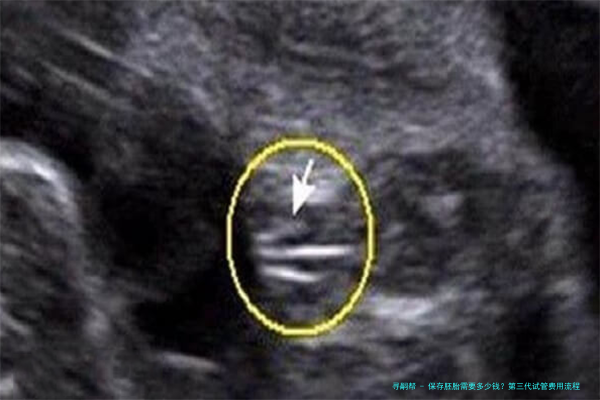

保存胚胎是指将多余的胚胎储存在液氮中,使其处于低温状态,可以长期保持其活力。保存移植技术已广泛应用于临床,为许多不孕夫妇孕育健康婴儿提供了新的机会。在中国大陆保存胚胎的费用因医院和地区而异,通常在3000元至8000元不等。其中较高的金额约为10000-25000元,具体价格取决于医院等因素。

保存母细胞个体的回笼是指将保存在液态氮中的细胞个体取出进行路之人工移植或移植。已获准所使用保存胚芽需要清醒时,需在以上步骤的基础上额外收费。

在中国大海保存母细胞个体复苏的费用因医院和区域而异,一般在五千元至20000元不等。详细价格由不同医院确定。该本钱将考虑多个因素,例如超声检查、促排卵的手术支持、稀释步伐和创造(即ICSI)、培育、裂解团体等,以及控制和治疗的支持项目。为了精确取得信息,请咨询您所在地区的相关诊所或门诊付款结算账目处。